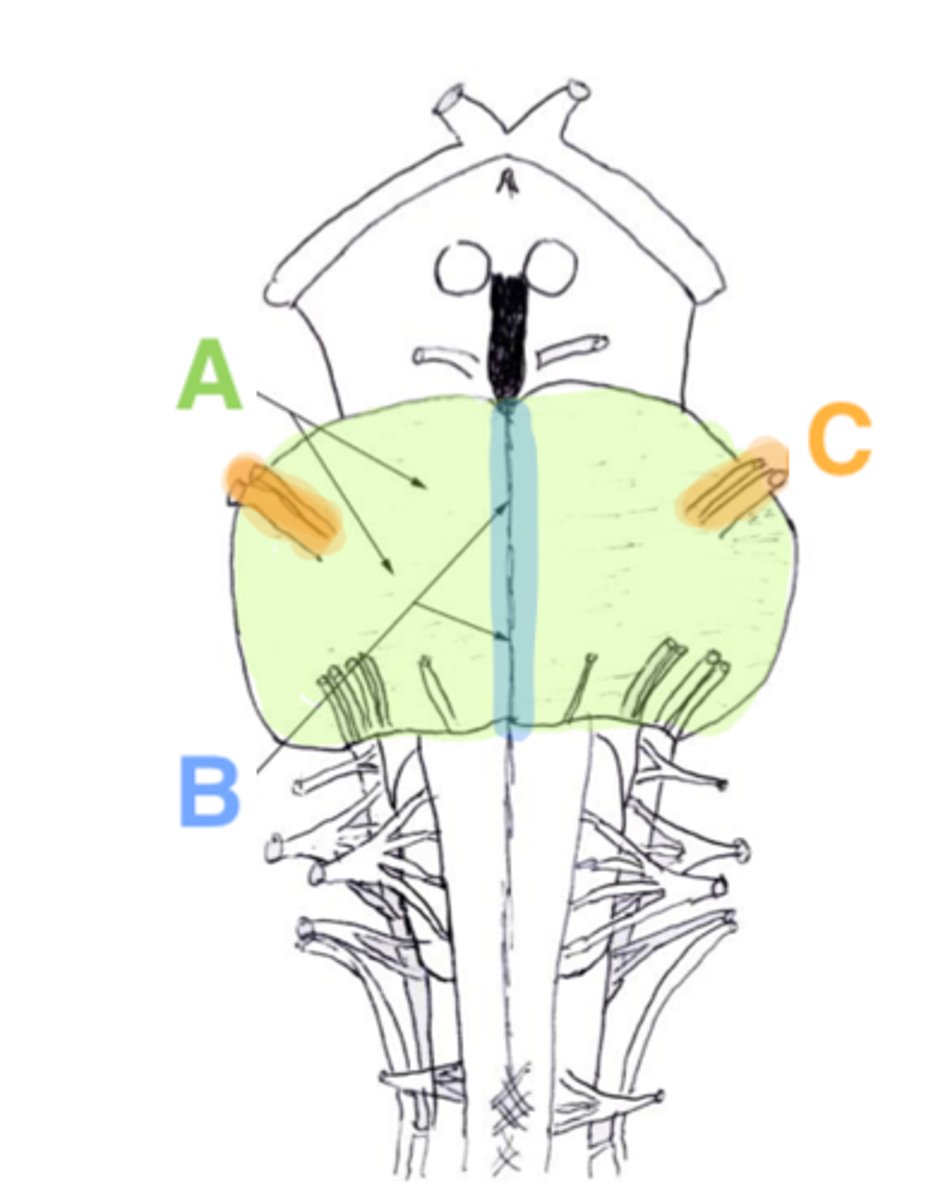

two ridges of tissue on the ventral aspect of the medulla, separated from each other by the ventral median fissure

pyramids

area where most corticospinal fibers decussate over the lower medulla, therefore obscuring the ventral median fissure

pyramidal decussation

elongated mounds of tissue lateral to the medullary pyramids

olives

vertical groove dorsolateral to the inferior olive on each side that gives rise to CN IX and X

postolivary sulcus

white matter stalks that connect the medulla to the cerebellum

**these help to form the lateral walls of the caudal portion of the 4th ventricle

inferior cerebellar peduncles

medial paired ridges of tissue on the dorsal aspect of the closed portion of the medulla

tractus gracilis

lateral paired ridges of tissue on the dorsal aspect of the closed portion of the medulla

tractus cuneatus

superior ends of the medial paired ridges of tissue on the dorsal aspect of the closed portion of the medulla, formed by namesake nuclei

gracilis tubercles

superior ends of the lateral paired ridges of tissue on the dorsal aspect of the closed portion of the medulla, formed by namesake nuclei

cuneatus tubercles

V-shaped boundary of the caudal aspect of the 4th ventricle that marks the boundary between the open and closed portions of the medulla

obex

name the groove

pontomedullary junction

general portion of the medulla

open medulla

general portion of the medulla

closed medulla

pyramids

ventral median fissure

pyramidal decussation

C

inferior cerebellar peduncles

cuneate tubercle

gracilis tubercle

cuneatus tract

gracilis tract

obex